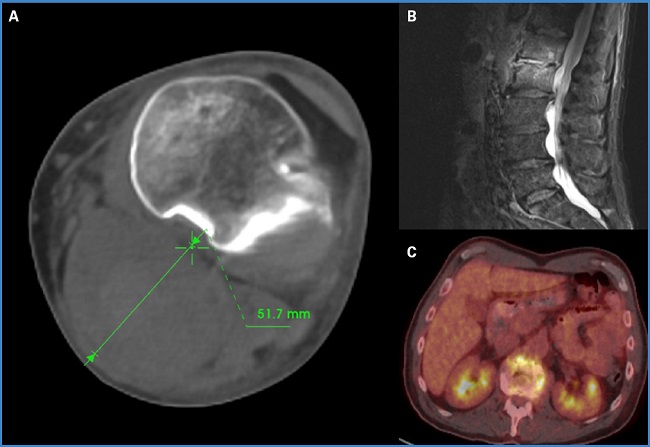

Al sexto día de hospitalización, experimentó un dolor súbito en el hueco poplíteo y un empeoramiento del edema infragenicular. Se realizó un eco Doppler, en el que se observó un importante hematoma, que no estaba presente en el estudio previo, que se extendía desde el muslo hasta el gemelo y el sóleo. Se le realizó una angio TC urgente del MII, que mostró un aumento de diámetro y la rotura del aneurisma poplíteo izquierdo (Fig. 2A).

Figura 2. A. Aneurisma poplíteo izquierdo con crecimiento de saco e imágenes sugestivas de rotura. B. RMN de columna lumbar con afectación de L1 y L2. C. PET-TC de columna vertebral con cambios sugestivos de espondilodiscitis.

Después de una adecuada evolución posquirúrgica, el paciente presentó dolor en la zona dorsolumbar que le limitaba la deambulación. En un PET-TC que se realizó como parte del estudio de extensión infecciosa, se observaron cambios en la columna vertebral al nivel de C7-D1 y L1-L2, sugestivos de espondilodiscitis, hallazgos que posteriormente se confirmaron en una resonancia magnética de la zona dorsolumbar (Fig. 2 B y C).